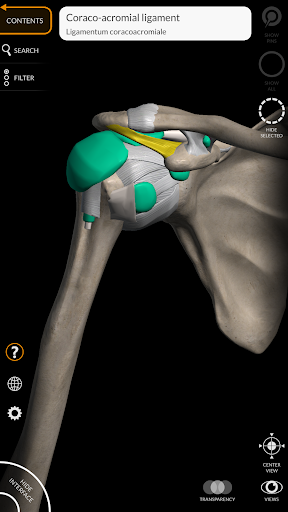

"Anatomía - Atlas 3D" permite estudiar la anatomía humana de forma fácil e interactiva.

A través de una interfaz sencilla e intuitiva es posible observar cada estructura anatómica desde cualquier ángulo.

Los modelos anatómicos 3D son especialmente detallados y con texturas de hasta una resolución de 4k.

nervioso • Sistema respiratorio • Sistema digestivo • Sistema urogenital (masculino y femenino) • Sistema endocrino • Sistema linfático • Sistema ocular y auditivo CARACTERÍSTICAS • Interfaz sencilla e intuitiva • Rotar y hacer zoom en cada modelo en el espacio 3D • Opción para ocultar o aislar uno o varios modelos seleccionados • Filtro para ocultar o mostrar cada sistema • Función de búsqueda para encontrar fácilmente cada parte anatómica • Función de marcador para guardar vistas personalizadas • Rotación inteligente que mueve el centro de rotación automáticamente • Función de transparencia • Visualización de músculos a través de niveles de capas desde las superficiales hasta las más profundas • Al seleccionar un modelo o un pin, aparece el término anatómico relacionado • Descripción de los músculos: origen, inserción, inervación y acción • Mostrar/ocultar interfaz de usuario (muy útil con pantallas pequeñas) MULTILINGÜE • Los términos anatómicos y la interfaz de usuario están disponibles en 11 idiomas: latín, inglés, francés, alemán, italiano, portugués, turco, ruso, español, Chino, japonés y coreano • Los términos anatómicos se pueden mostrar en dos idiomas simultáneamente REQUISITOS DEL SISTEMA • Android 8.0 o posterior, dispositivos con al menos 3 GB de RAM Reversi

Ligamentos agregados